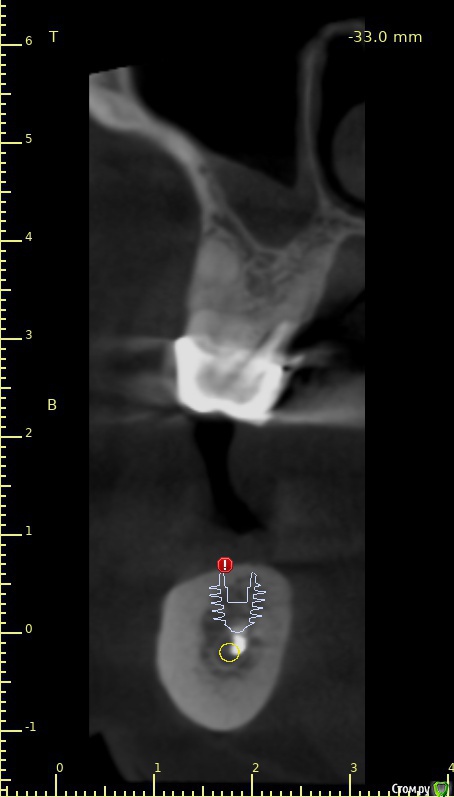

3й квадрант. Я могу обойти нерв. И даже выйти в более-менее приемлемую ортопедическую позицию.

Но очень смущает высота коронки и соотношение этой высоты к параметрам имплантата...

В 4м квадранте очень красиво стают штрауман коротышки TL. Но в позиции 6го много пломбировочной массы (остатки). не хотелось бы с таким ценником расширять показания: ставить близко к нерву, делать мост и тем более делать высокие коронки.